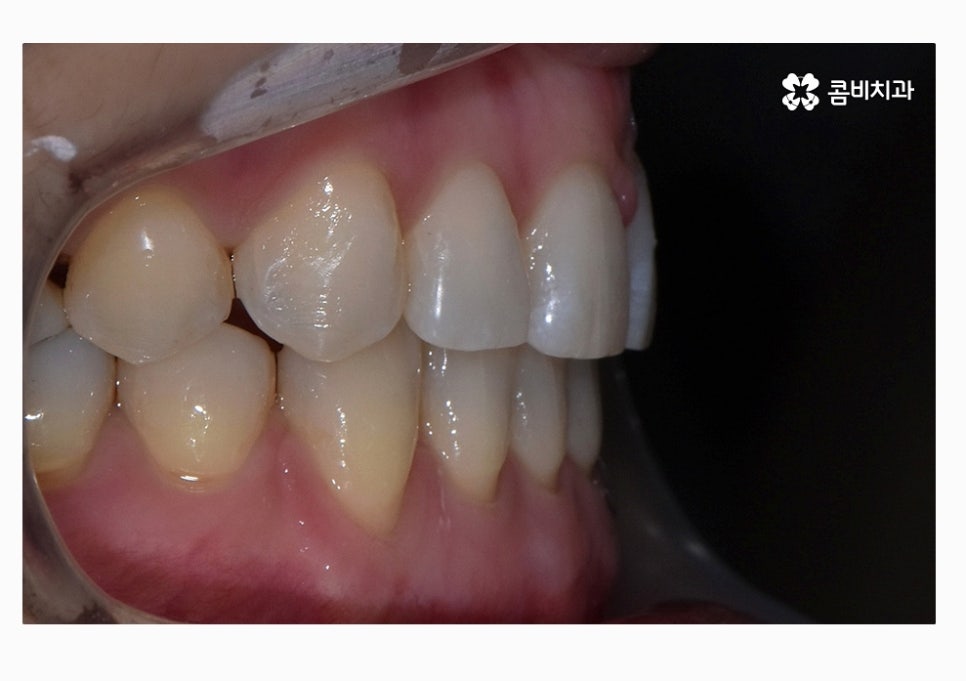

치열 사진을 볼 때 정면보다는 옆모습으로 볼 때

아래 어금니가 위 어금니보다 앞으로 나와있고

앞니 교합이 제대로 맞물리지 않는다는 것이 눈에 띄게 나타나는데

위 환자분의 경우에는 콤비교정의 치료 경과를 보면

아랫니가 정상교합이 되었고 치열도 보다 가지런하게

변화되고 있음을 알 수 있는데요.

위 케이스는 총 1년 9개월 정도의 치료 기간이 소요되었으며,

개개인마다 치료 결과와 기간은 차이가 있을 수 있습니다.